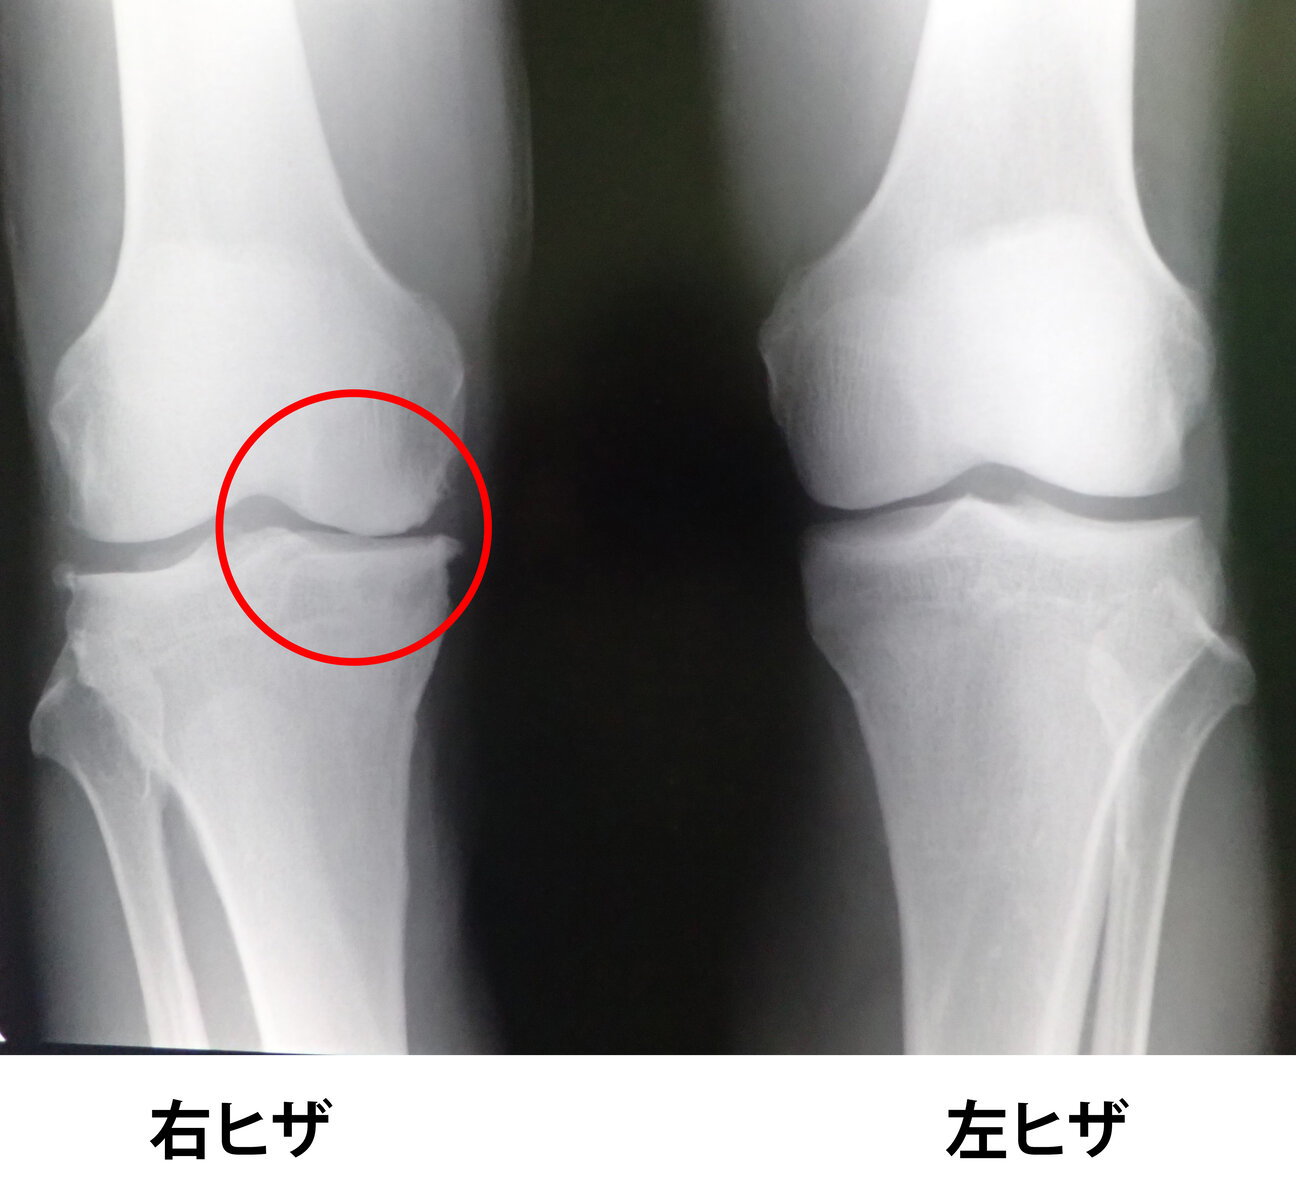

@ucF62EIaou2VtDg返信先:@saki_totsuka 膝とお皿の上らへんだと、半月板損傷とか、膝軟骨の変形とかが考えられます。

@setsuzeidai0返信先:@momoyamatencyo おはようございます☀ 今日も元気にいきましょう♪ オイラも元々持病を持っている上、おとといから膝が激痛 🧑⚕️診てもらったら膝軟骨がダメに😵 もう完全に老人突入です。 桃山さんはまだ50歳前、今のうちに充分ケアして元気パーフェクトの回復して下さい。